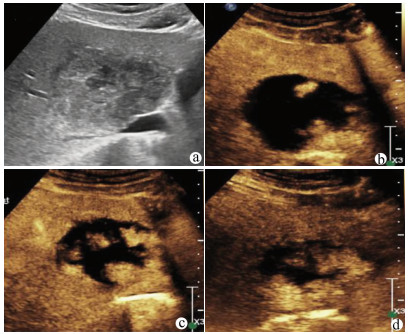

肝病超声诊断指南

中华医学会超声医学分会, 中国研究型医院学会肿瘤介入专业委员会, 国家卫生和健康委员会能力建设和继续教育中心超声医学专家委员会

2021, 37(8): 1770-1785. DOI: 10.3969/j.issn.1001-5256.2021.08.007

摘要(3138) HTML (6640) PDF (9311KB)(810)

超声检查无创、实时、价廉,无辐射、便于反复进行,是最常用的肝脏影像学检查方法。近年来,超声检查新技术如超声造影、弹性成像发展迅速,可有效鉴别肝内占位性病变性质、评估肝纤维化和门静脉高压程度以及监测肝病治疗效果,在临床肝病及其介入治疗中发挥重要诊断价值。本指南规范了肝病多模态超声技术(灰阶超声、彩色多普勒超声、超声造影、弹性超声)检查的仪器调置、患者准备及医生检查方法;对肝脏弥漫性病变(炎性病变、纤维化、硬化)、多种占位性病变及肝病介入操作的多模态超声技术诊断标准进行了定义和规范,同时推荐了超声监测周期及肝脏疾病超声诊断报告书写规范。